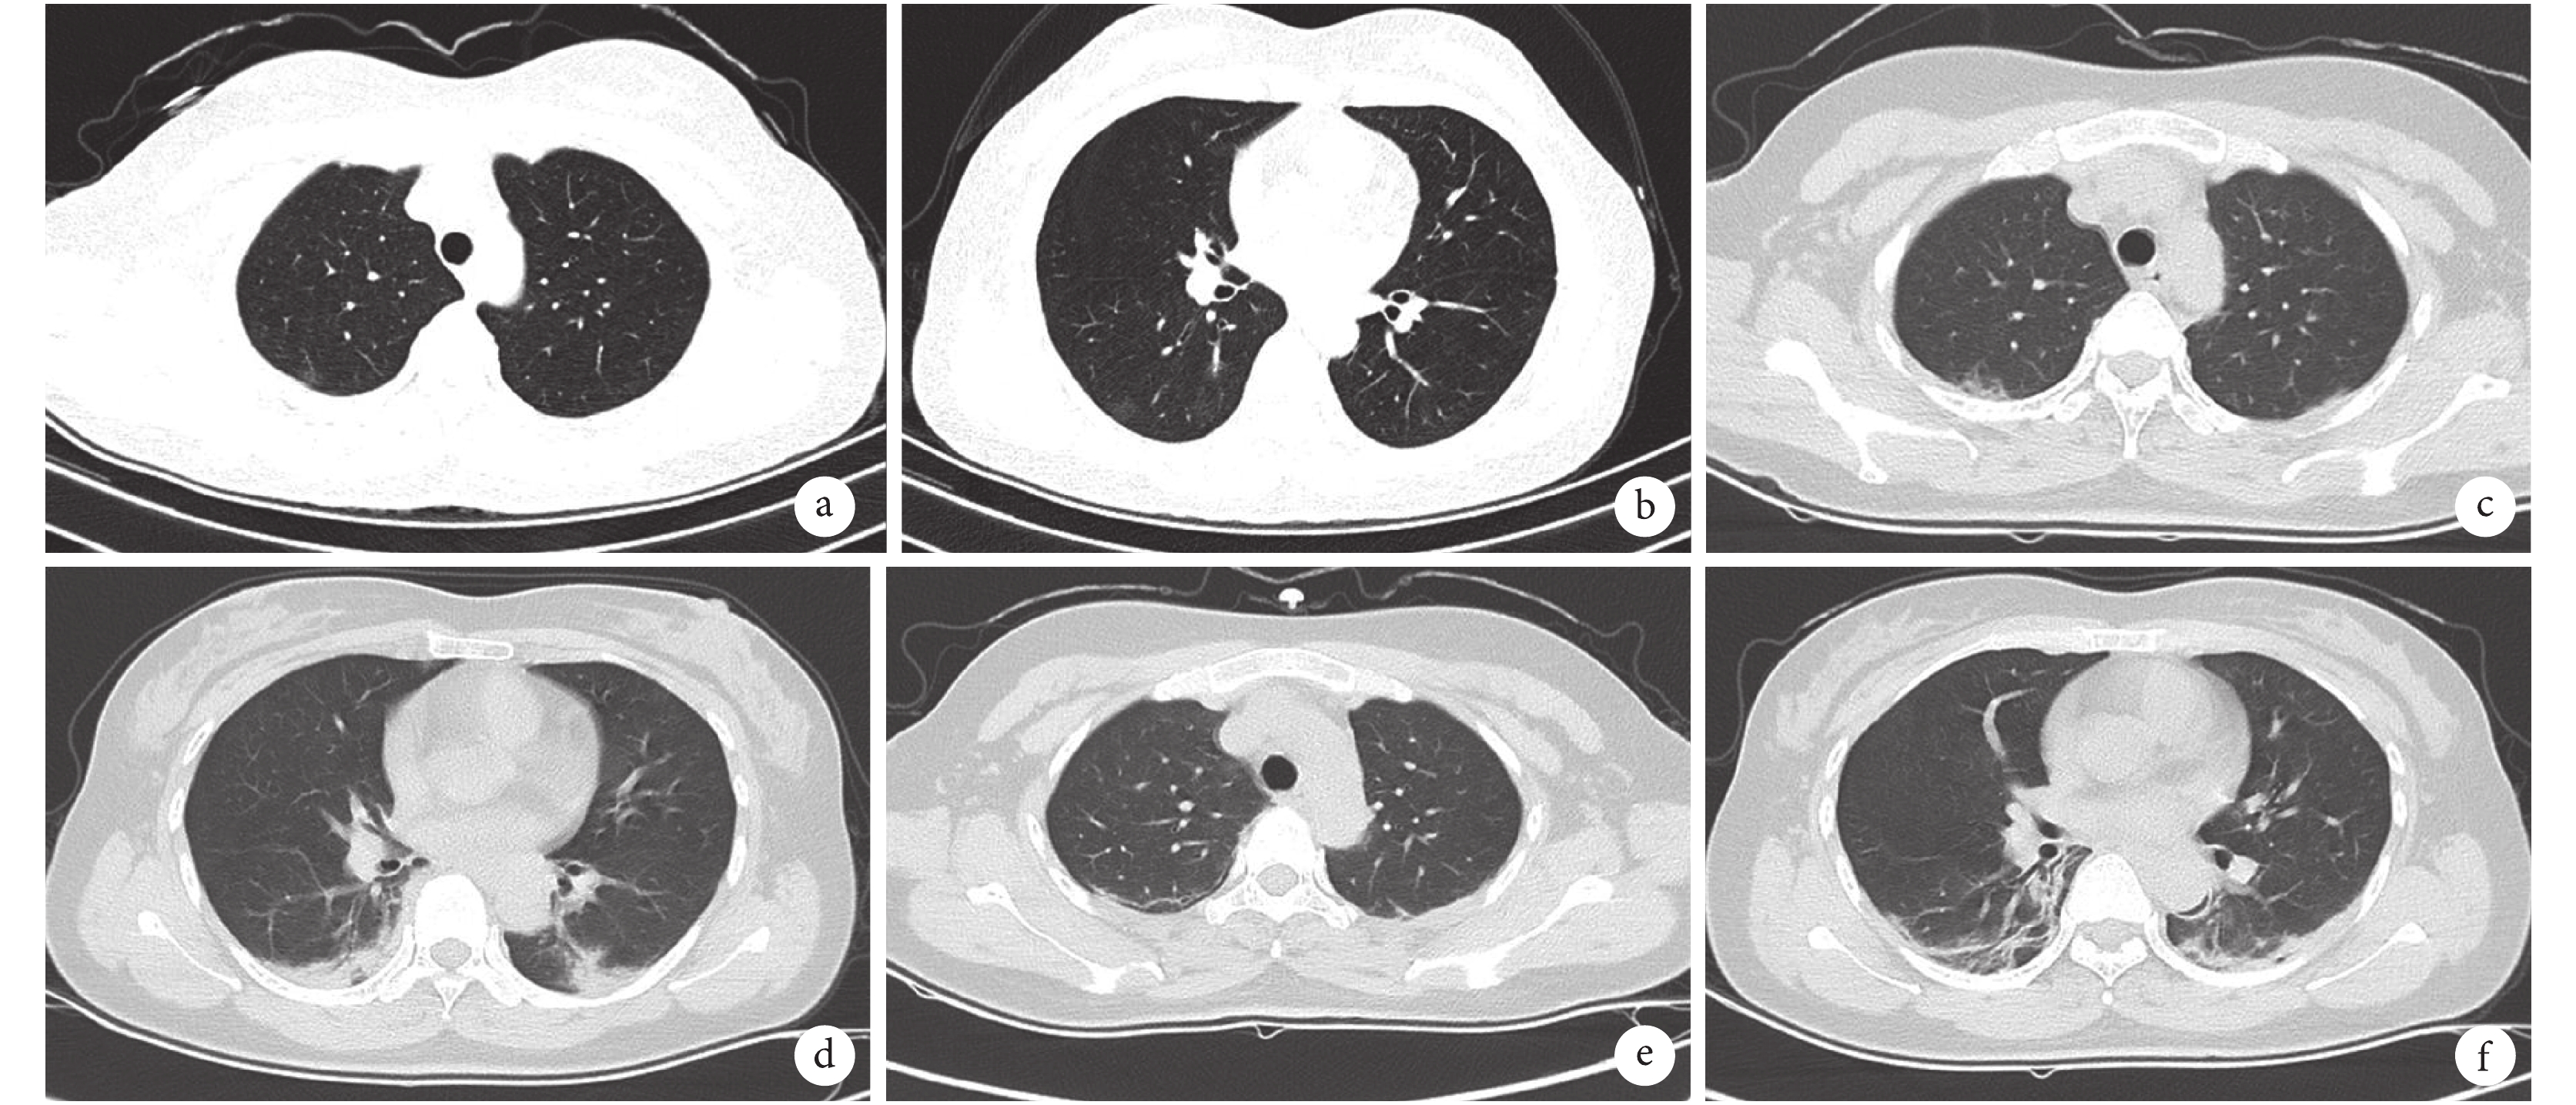

圖2

新冠肺炎患者胸部 CT 檢查像

女性,37 歲,發熱、乏力 6 d 入院。入院時,雙肺散在斑片狀滲出影(a、b);入院第 5 天,雙肺可見斑片狀滲出影(c、d);入院第 9 天,雙肺 CT 提示條索狀改變(e、f)

49 例患者中,47 例(95.9%)出現了單發或散在多發的斑片狀磨玻璃密度影(圖 1),部分患者出現了實變影和支氣管充氣征等,以中下葉胸膜下為著。病灶累及范圍廣,平均累及 2.8 個肺葉。2 例(4.1%)患者入院時肺部無明顯表現,但在病情進展過程中逐漸出現了斑片狀磨玻璃樣改變(圖 2)。重型/危重型患者與普通型患者相比,肺部 CT 顯示病灶范圍更廣(平均累及 3.4 個肺葉)(圖 3),但差異無統計學意義(P=0.253)。